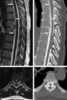

Disk extrusion

Spinal disc herniation is an injury to the cushioning and connective tissue between vertebrae, usually caused by excessive strain or trauma to the spine. It may result in back pain, pain or sensation in different parts of the body, and physical disability. [Source: Wikipedia ]